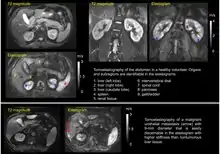

Tomoelastography of the abdomen of a healthy volunteer and a patient

Tomoelastography of the abdomen; upper a healthy state, lower with malignancy.